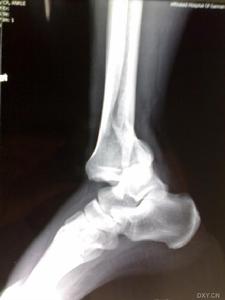

你的X線片上看,應為2型,屬可作可不作的一種。

你的前臂是否有機械性阻擋,應該到醫院來檢查以下,如果有則應該早期手術。反之,可以保守治療。這點很重要,尤其是對將來肘關節的功能維護。如果需要手術時,對肘關節功能要求高,可考慮行切開內固定術;要求一般,可行橈骨小頭的切除術。